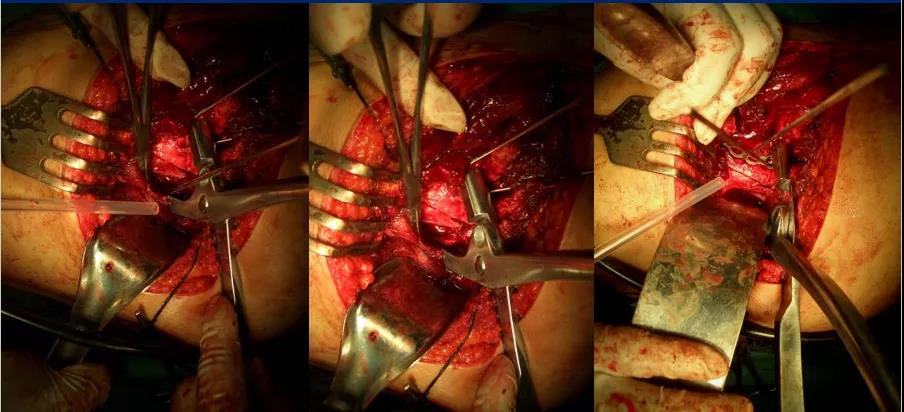

后方K—L入路联合前方髂腹股沟微创入路治疗复杂髋臼骨折:

2、一般先选择骨折移位大、粉碎较严重的后柱后壁骨折一侧 3、常先采取Kocher-Langenbeck后入路切口,改半俯卧位;切口:髂后上棘外下4cm处→经大转子顶点→ 垂直向下约5cm, 显露后柱后壁骨折

4、 以骨撬分别放在髂棘、坐骨大切迹、坐骨小切迹,显露后柱后壁骨折

5、根据CT情况探查关节腔,清除关节内的碎骨片; 6、a:解剖复位髋臼后柱及后壁;b:以重建钢板固定 c:纱布填塞切口 d:行C型臂透视了解前壁或前柱骨折复位情况;

7、后柱后壁解剖复位后,由于关节囊完整,前柱一般都能自然复位,对于后柱复位后,前柱骨折移位仍明显且复位该部位能明显修复整个髋臼的解剖序列和减少术后并发症的枢纽部位作为前入路的切开部位。前入路微创切口沿髂耻嵴插板,行前柱重建钢板内固定;

8、若采取前路髂腹股沟入路,改半仰卧位;切口:髂嵴和耻骨联合上;2 cm 两部位取切口;腹股沟区域不予切开显露

9、根据需要分别暴露前壁及前柱骨折部位:术中注意避免损伤髂腰肌及股神经束、髂外血管、精索或圆韧带死亡冠动脉

10、沿髂耻嵴插板,在耻骨上支用2枚螺钉固定,维持前柱,前壁解剖序列连续性,再髂骨上固定另一枚螺钉,起到断端加压作用。

微创插板病历后路有限切开,结合前路微创插板内